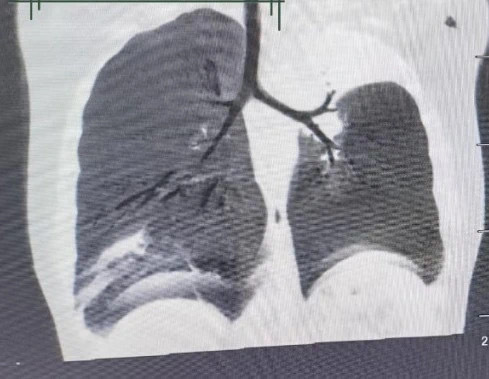

呼吸内科专家发现患儿咳嗽剧烈、呼吸急促,肺部CT检查结果显示患儿左肺上叶实变、有胸腔积液,肺内病变严重,诊断为重症肺炎。排除新冠病毒感染后,月月被收入呼吸内科病房治疗。